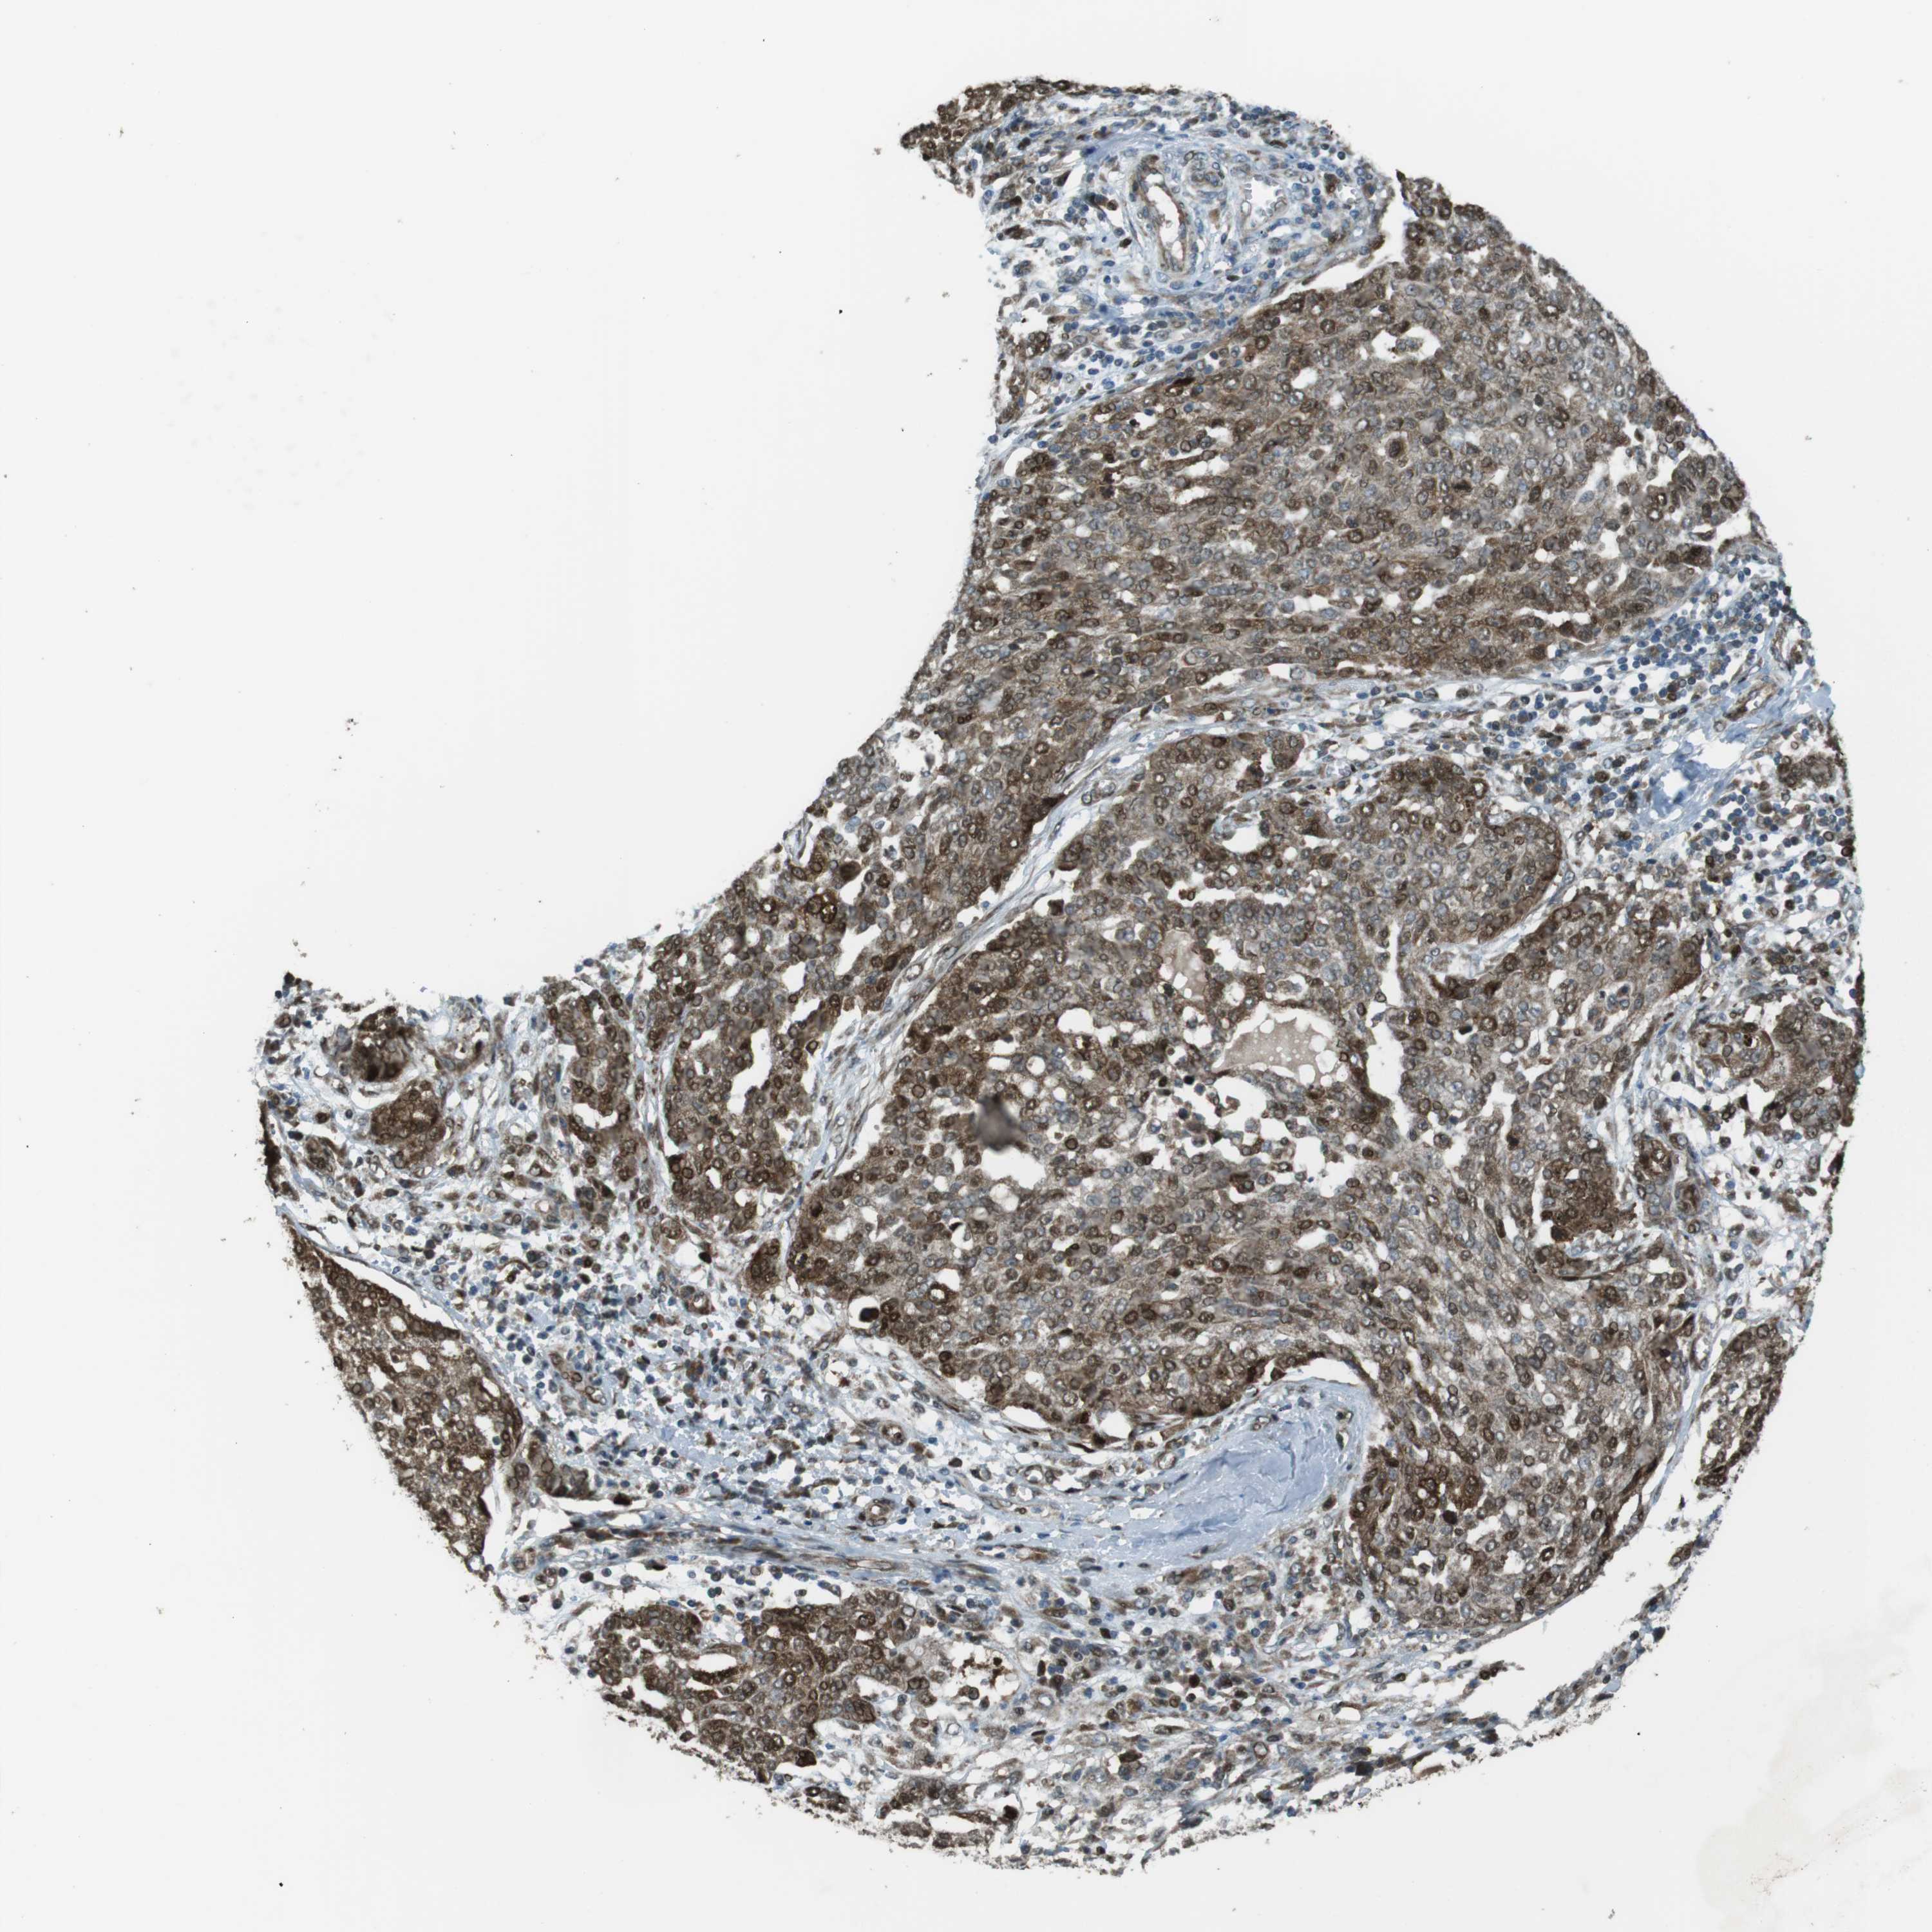

OVARIAN CANCER - Protein expressioni

A mouse-over function shows sample information and annotation data. Click on an image to view it in a full screen mode. Samples can be filtered based on level of antibody staining by selecting one or several of the following categories: high, medium, low and not detected. The assay and annotation is described here.

Note that samples used for immunohistochemistry by the Human Protein Atlas do not correspond to samples in the TCGA dataset.

Antibody stainingi

Antibody staining in the annotated cell types in the current human tissue is reported as not detected, low, medium, or high, based on conventional immunohistochemistry profiling in selected tissues. This score is based on the combination of the staining intensity and fraction of stained cells.

Each image is clickable and will lead to virtual microscopy that enables deeper exploration of all samples and also displays staining intensity scores, fraction scores and subcellular localization as well as patient and tissue information for each sample.

Antibody HPA015705

Staining

High

Medium

Low

Not detected

Intensity

Strong

Moderate

Weak

Negative

Quantity

>75%

75%-25%

<25%

None

Location

Nuclear

Cytoplasmic/membranous

Cytoplasmic/membranous,nuclear

Cystadenocarcinoma, serous, NOS

Carcinoma, endometroid

Cystadenocarcinoma, mucinous, NOS

Carcinoma, NOS